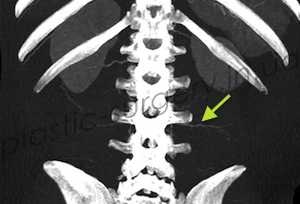

После предварительной локации точки выхода сосудов в покровные ткани в области поясницы, рядом с раневым дефектом с помощью аудио-допплера, больному было проведено более детальное обследование – КТ с ангиографией. При проведении исследования была визуализирована одна из люмбальных артерий и её перфорант справа от позвоночника, уточнено место выхода перфоранта, направление его оси и ветвление в покровных тканях (Рис. 3, 4, 5).

Рис. 3. Снимок компьютерной томографии с ангиографией, стрелкой отмечена люмбальная артерия. (слева).